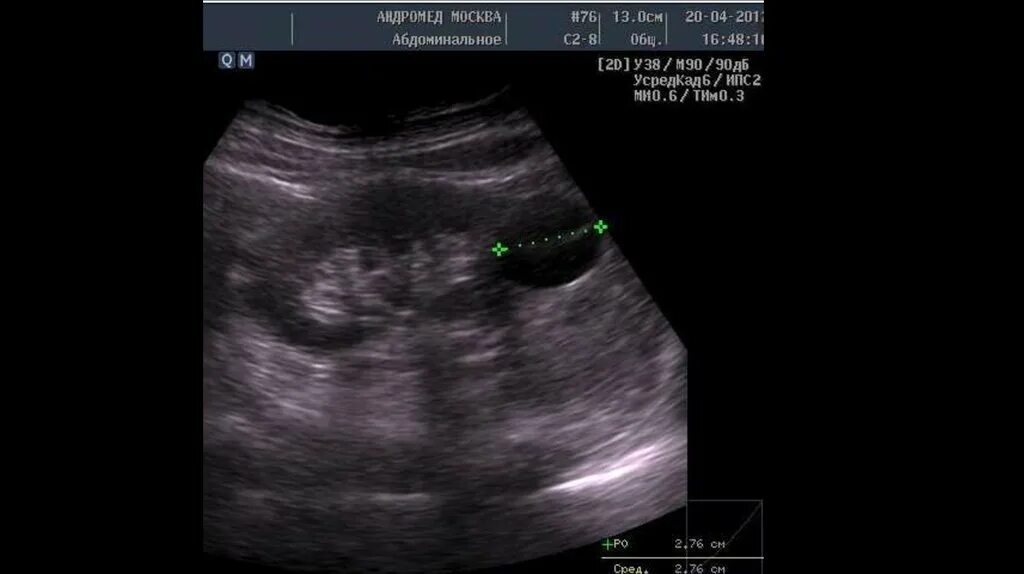

Белое пятно на узи